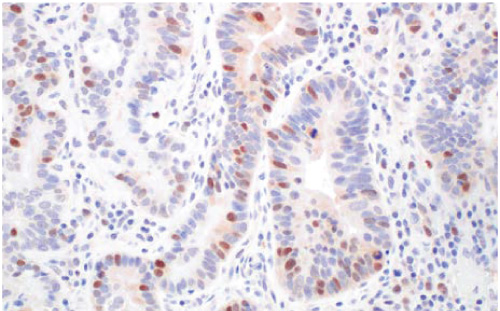

Rad51 (F4L4Y) Rabbit Monoclonal

Antibody #84555

IHC-P: IHC analysis of paraffin-embedded human esophageal carcinoma using #84555.

A key protein in DNA double-strand break repair

Cells sense and repair DNA double-strand breaks (DSBs) through two signaling pathways: non-homologous end joining (NHEJ) and homologous recombination (HR). Rad51 regulates HR by polymerizing filaments along single-stranded DNA through interactions with Rad54 and BRCA2. Five Rad51 paralogs (XRCC2, XRCC3, Rad51B, Rad51C, and Rad51D) exist in vertebrates, and all are thought to be required

for efficient HR. RAD51 is overexpressed in over 20 types of cancer and has been associated with reduced overall survival in at least 10 cancers. It is therefore a promising biomarker for various cancers. #84555 is suitable for WB, IP, and IHC-P using human, mouse, rat, and monkey samples.